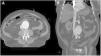

Paciente varón de 71 años, con antecedentes de hipertensión arterial y monorreno (riñón único derecho). Acude a consulta por dolor súbito en fosa iliaca derecha irradiado a ingle ipsilateral. A la exploración se encuentran masa pulsátil infraumbilical y soplo continuo en mesogastrio. Ingresa en Unidad de Cuidados Intensivos (UCI) obnubilado con marcada inestabilidad hemodinámica y taquicárdico. En la tomografía computarizada (TC) de abdomen basal se observa un gran aneurisma de aorta abdominal infrarrenal con signos de sangrado perianeurismático (flecha en fig. 1). Tras la administración de contraste se objetiva comunicación entre la pared posterolateral derecha del aneurisma y la vena cava inferior, compatible con una fístula aortocava (flecha en corte axial fig. 2A y coronal 2B). Los hallazgos se confirman en la reconstrucción tridimensional realizada (fig. 3). Se decidió colocación de endoprótesis por parte de cirugía cardiovascular. Finalmente, el paciente presentó episodio de colitis isquémica y choque séptico, siendo exitus a los siete días.